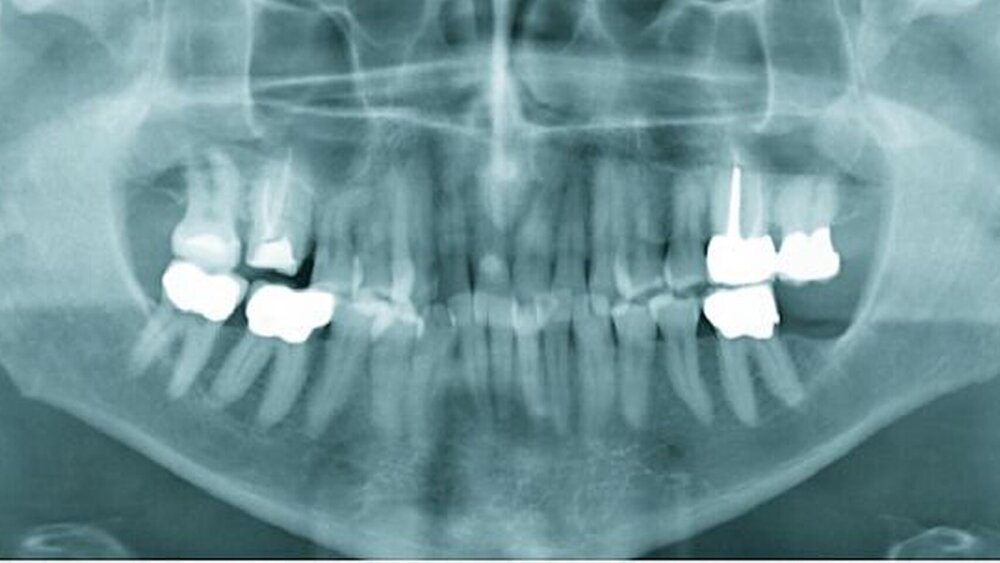

Röntgenologisch war eine geringgradige parodontale Destruktion mit generalisiert horizontalem Knochenabbau im Bereich des Oberkiefers sichtbar (Abbildung 1b). Die Auswertung des Fernröntgenseitenbildes zeigte eine neutrale Bisslage.